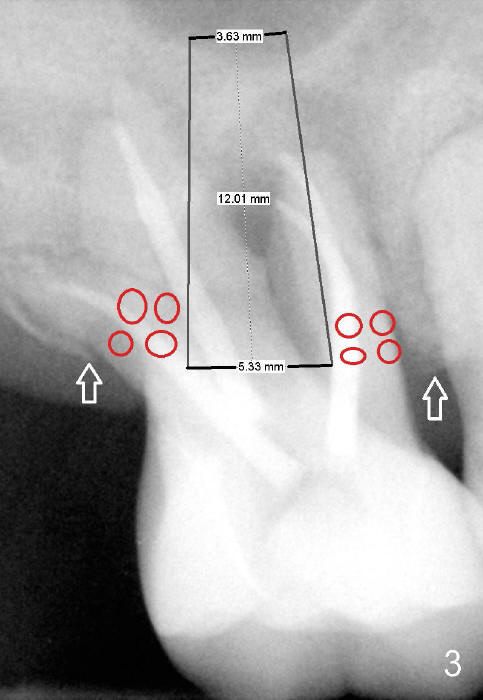

A 60-year-old man has poor dentition (Fig.1). The tooth #3 is symptomatic with a mesiobuccal fistula. PA shows large periapical radiolucency associated with the mesiobuccal root (Fig.2 *). It appears that the tooth is non-salvageable. The roots of this tooth are widely furcated. The septum should be large unless destroyed by infection.